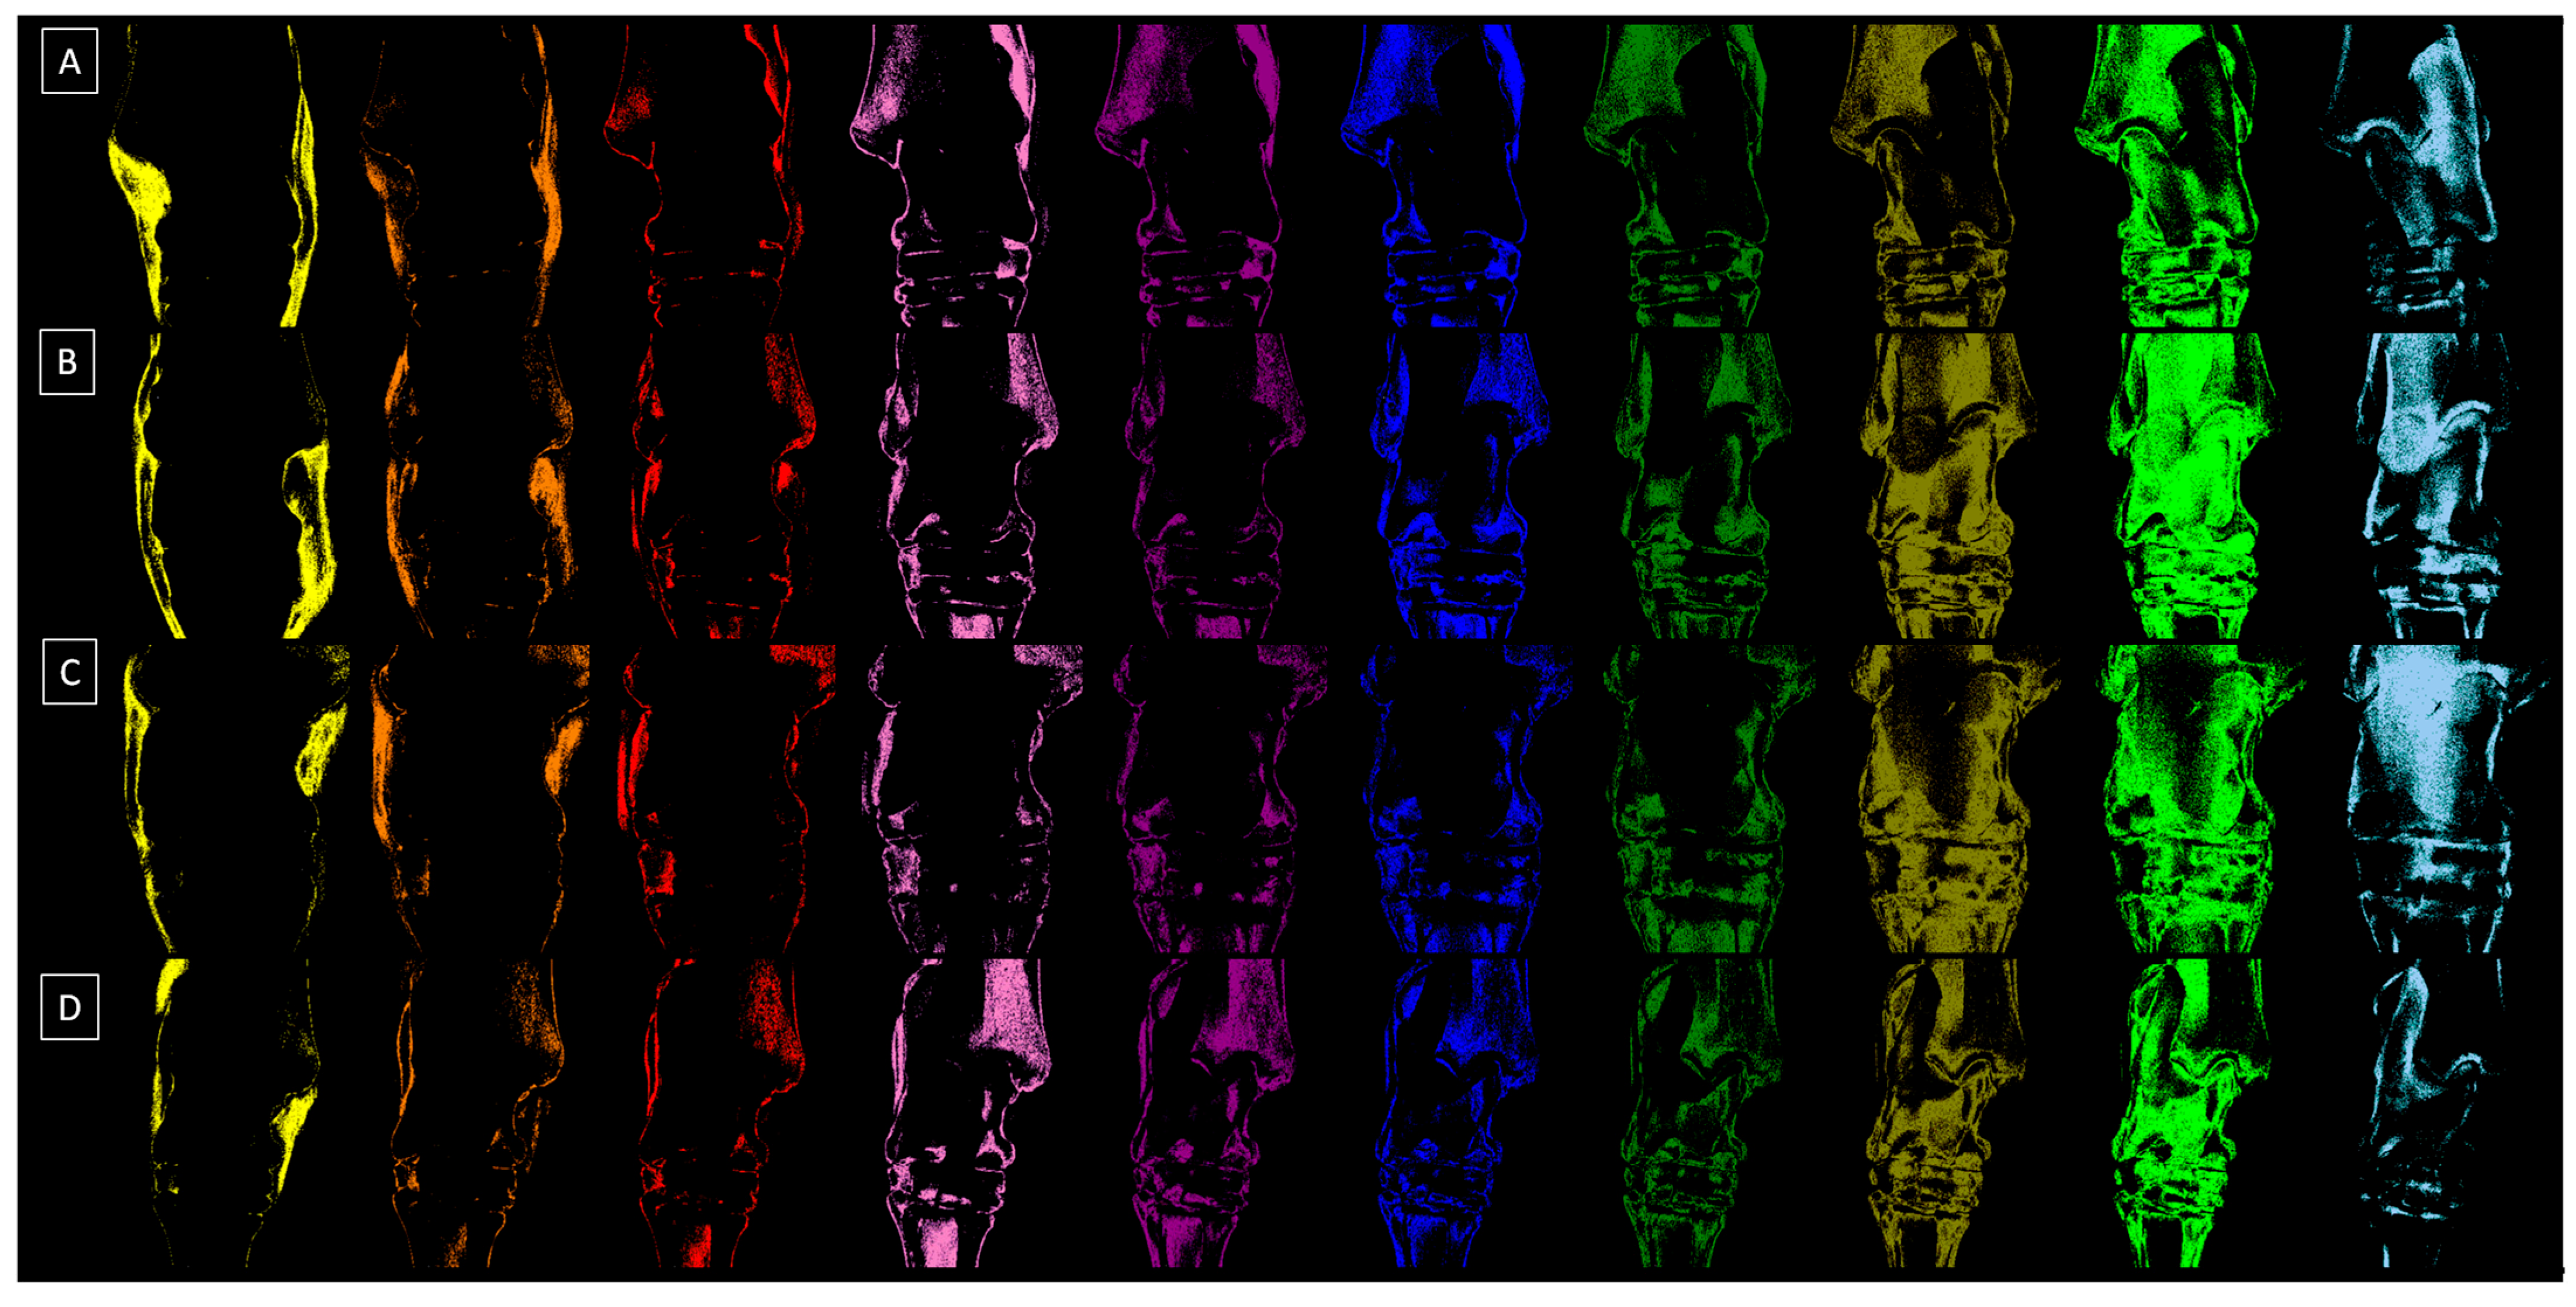

2.2. Radiograph Processing

2.3. Radiograph Quantification

| Grade | Severity | Radiographic Signs |

|---|---|---|

| 0 | Normal | Normal width and shape of the joint space; smooth cortical bone surface; normal subchondral bone pattern; no periosteal proliferation; no intra-articular mineralization |

| 1 | Mild | Narrow and irregular joint space with osteophytes; irregular cortical bone surface with well-defined protuberance; smooth subchondral bone pattern; flat periosteal proliferation; mild intra-articular mineralization |

| 2 | Moderate | Narrow and irregular joint space with multiple osteophytes, enthesiophytes, and marked asymmetry; irregular cortical bone surface with well-defined bone proliferation; subchondral bone cyst; flat periosteal proliferation; moderate intra-articular mineralization |

| 3 | Severe | Completely narrow joint space with large osteophytes and enthesiophytes; severe deformation of cortical bone surface; subchondral bone sclerosis; flat or intense periosteal proliferation; severe intra-articular mineralization |